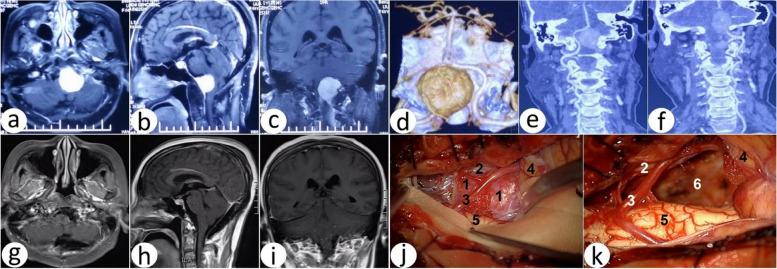

We retrospectively analyzed 76 patients with FMM and classified them into two classifications, classification ABS according to the relationship between the FMM and the brainstem and classification SIM according to the relationship between the FMM and the vertebral artery (VA). All patients underwent either the far lateral approach (54 cases) or the suboccipital midline approach (22 cases).

Of the 76 cases, 47 cases were located ahead of the brainstem (A), 16 cases at the back of the brainstem (B), and 13 cases were located laterally to the brainstem (S). There were 15 cases located superior to the VA (S), 49 cases were inferior (I), and 12 cases were mixed type (M). Among 76 cases, 71 cases were resected with Simpson grade 2 (93.42%), 3 with Simpson grade 3 (3.95%), and 2 with Simpson grade 4 (2.63%). We summarized four anatomical triangles: triangles SOT, VOT, JVV, and TVV. The mean postoperative Karnofsky performance score was improved in all patients (p < 0.05). However, several complications occurred, including hoarseness and CSF leak.

ABS and SIM classifications are objective indices for choosing the surgical approach and predicting the difficulty of FMMs, and it is of great importance to master the content, position relationship with the tumor, and variable anatomical structures in the four "triangles" for the success of the operation.